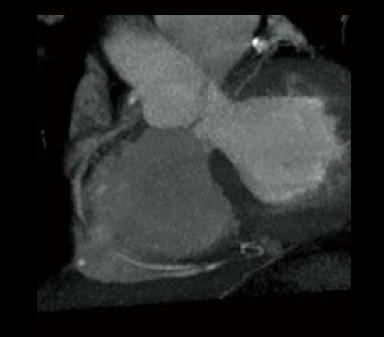

Cardio StillShot : OFF

ON